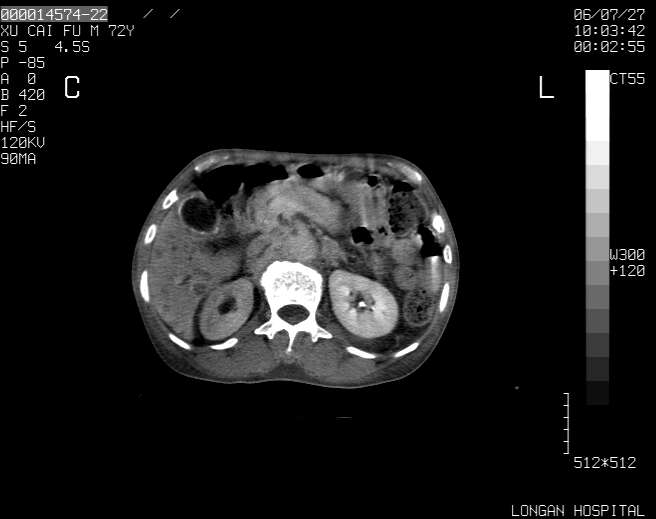

以下是引用winter在2006-7-30 20:14:00的发言:[br]1、考虑胆囊癌伴胆道侵犯并高位胆道梗阻、肝内多发转移、腹膜后淋巴结转移。[br]2、右肾轻度积水。[br]3、老人家72岁了胰腺头体尾部均较饱满,不过未见密度异常及其他异常征象。[br]4、腹水。

以下是引用jiajie在2006-7-31 7:10:00的发言:[br]考虑肝转移瘤,腹膜后淋巴结增大。[br]胃癌不能除外,建议胃镜检查。